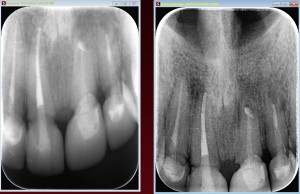

How to figure out when a root canal treatment is correct?

The root canal treatment is recommended when the nerve and the blood supply of the...